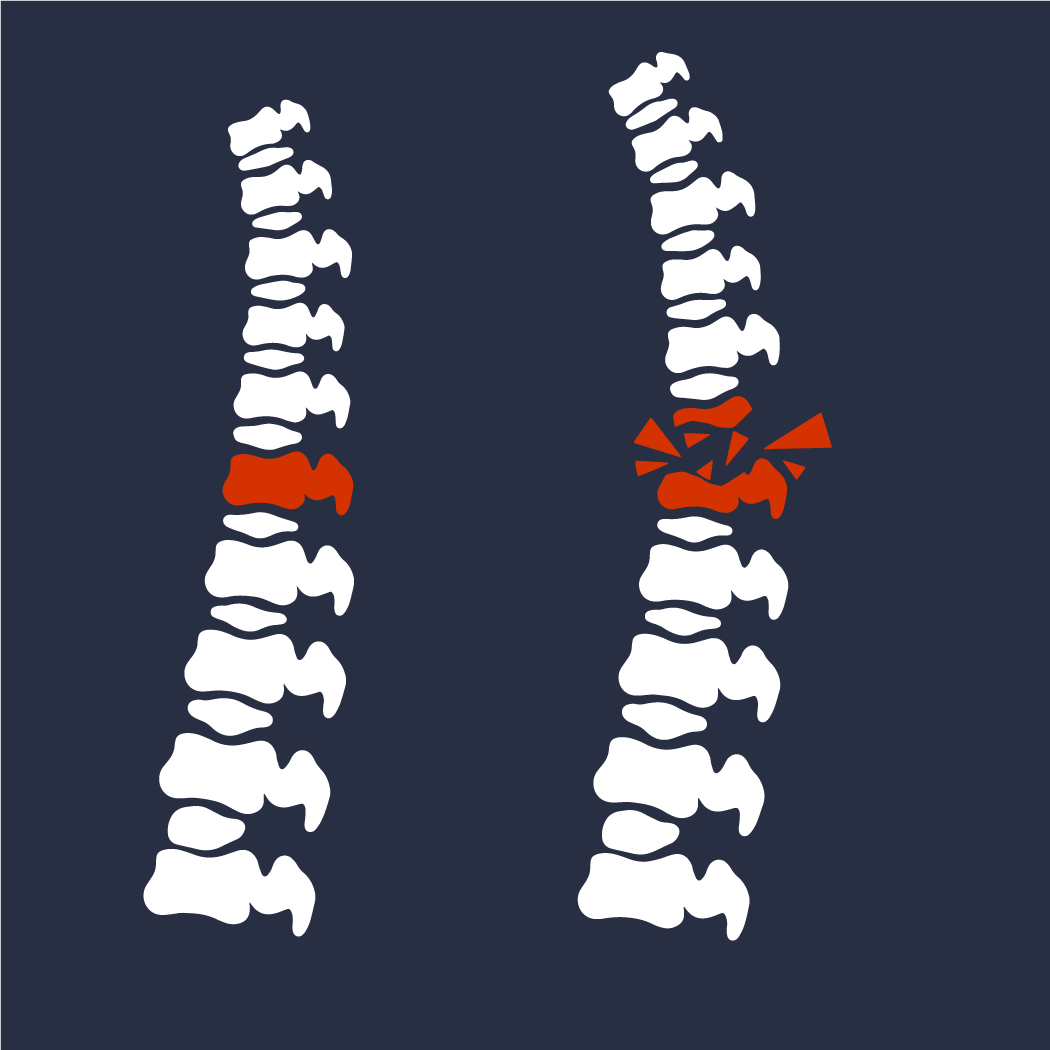

Disco roto

La ruptura de disco vertebral es una lesión en la columna vertebral que se produce cuando el disco intervertebral se desgarra o se desgasta. Esto puede ocurrir debido a la edad, lesiones o enfermedades degenerativas de la columna vertebral.

Los síntomas de una ruptura de disco vertebral pueden incluir dolor en la espalda, debilidad muscular, entumecimiento, hormigueo o calambres en los brazos o en las piernas. La ruptura de disco vertebral puede ser tratada con una combinación de terapia física, medicamentos para el dolor y a veces, cirugía.

Hernia de disco

La hernia de disco es una afección dolorosa causada por la degeneración de la unión entre dos vértebras. Esto se debe a que, con el paso del tiempo, la almohadilla de tejido conocida como disco intervertebral, que actúa como amortiguador entre las vértebras, se desgasta. Esto hace que el disco pierda su flexibilidad y se abra, lo que permite que parte del contenido del disco salga fuera de su lugar.

Esta parte del disco que se desplaza puede presionar un nervio en la espalda y provocar dolor, entumecimiento, hormigueo o debilidad en la parte afectada. El tratamiento para la hernia de disco incluye medicamentos para el dolor, terapia física, terapia física, ejercicios de estiramiento, inyecciones de esteroides y, en casos graves, cuando el problema no ha cedido ante estos métodos conservadores, es necesaria la cirugía para reparar el disco dañado.

Compresión de la médula espinal

Esta condición ocurre cuando hay una presión excesiva en la médula espinal, causada por una acumulación de tejido, parte del hueso, quistes, tumores u otros elementos que limitan el flujo de sangre y afectan el suministro de oxígeno y nutrientes a la médula espinal.

¿Cuáles son los síntomas? Puede tener una variedad de síntomas, dependiendo de la ubicación de la compresión y de la cantidad de tejido afectado. Estos síntomas pueden incluir dolor, entumecimiento, adormecimiento, debilidad muscular, disminución del reflejo, dificultad para controlar la vejiga o los intestinos, y problemas de equilibrio. La compresión de la médula espinal puede tratarse con medicamentos, cirugía o terapia física.